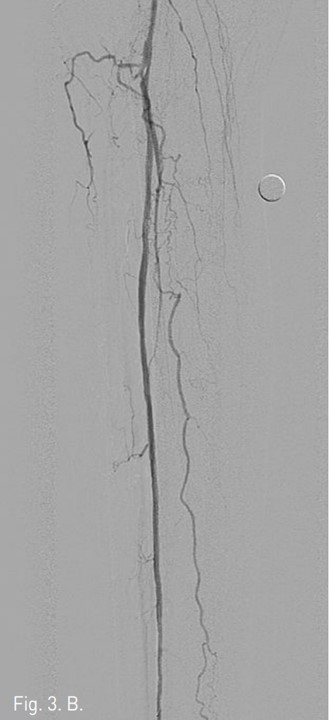

Fig. 3. A

Fig. 3. A. A U-looped wire tip is passed along the subintimal channel of occluded left peroneal artery.

Fig. 3. B

B. Completion angiogram of left pffoneal artery after subintimal angioplasty. Complete restoration of arterial flow in peroneal artery.

일단 후경골 동맥은 그대로 두고, TP trunk에서 0.016 inch guide wire(GT guide wire, Terumo, Japan)을 사용하여 막혀 있는 비골동맥의 입구에서 subintimal guide wire passage한 다음 (Fig. 3A) 비골동맥의 원위부 true lumen으로 re-entry가 되었다. 3mm/10cm long balloon (SAVVY, CORDIS, Miami, USA))으로 우측 비골동맥 에 대해 subintimal angioplasty를 시행하였으며 우측 비골동맥의 혈류는 재개통 되었다 (Fig. 3B).